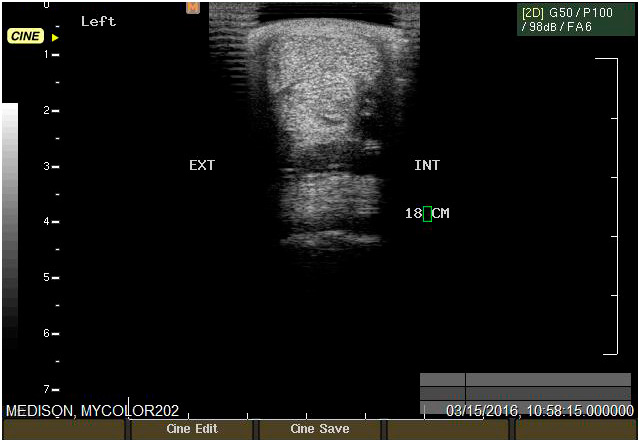

Ecografía

Cuenta con Ecografía digital de alta complejidad.

17 años de experiencia siendo una de las ecografistas más reconocidas en la práctica de equinos. Realiza pasantías en la universidad de Davis California y en Mid-Atlantic Equine Medical Center en New Jersey.